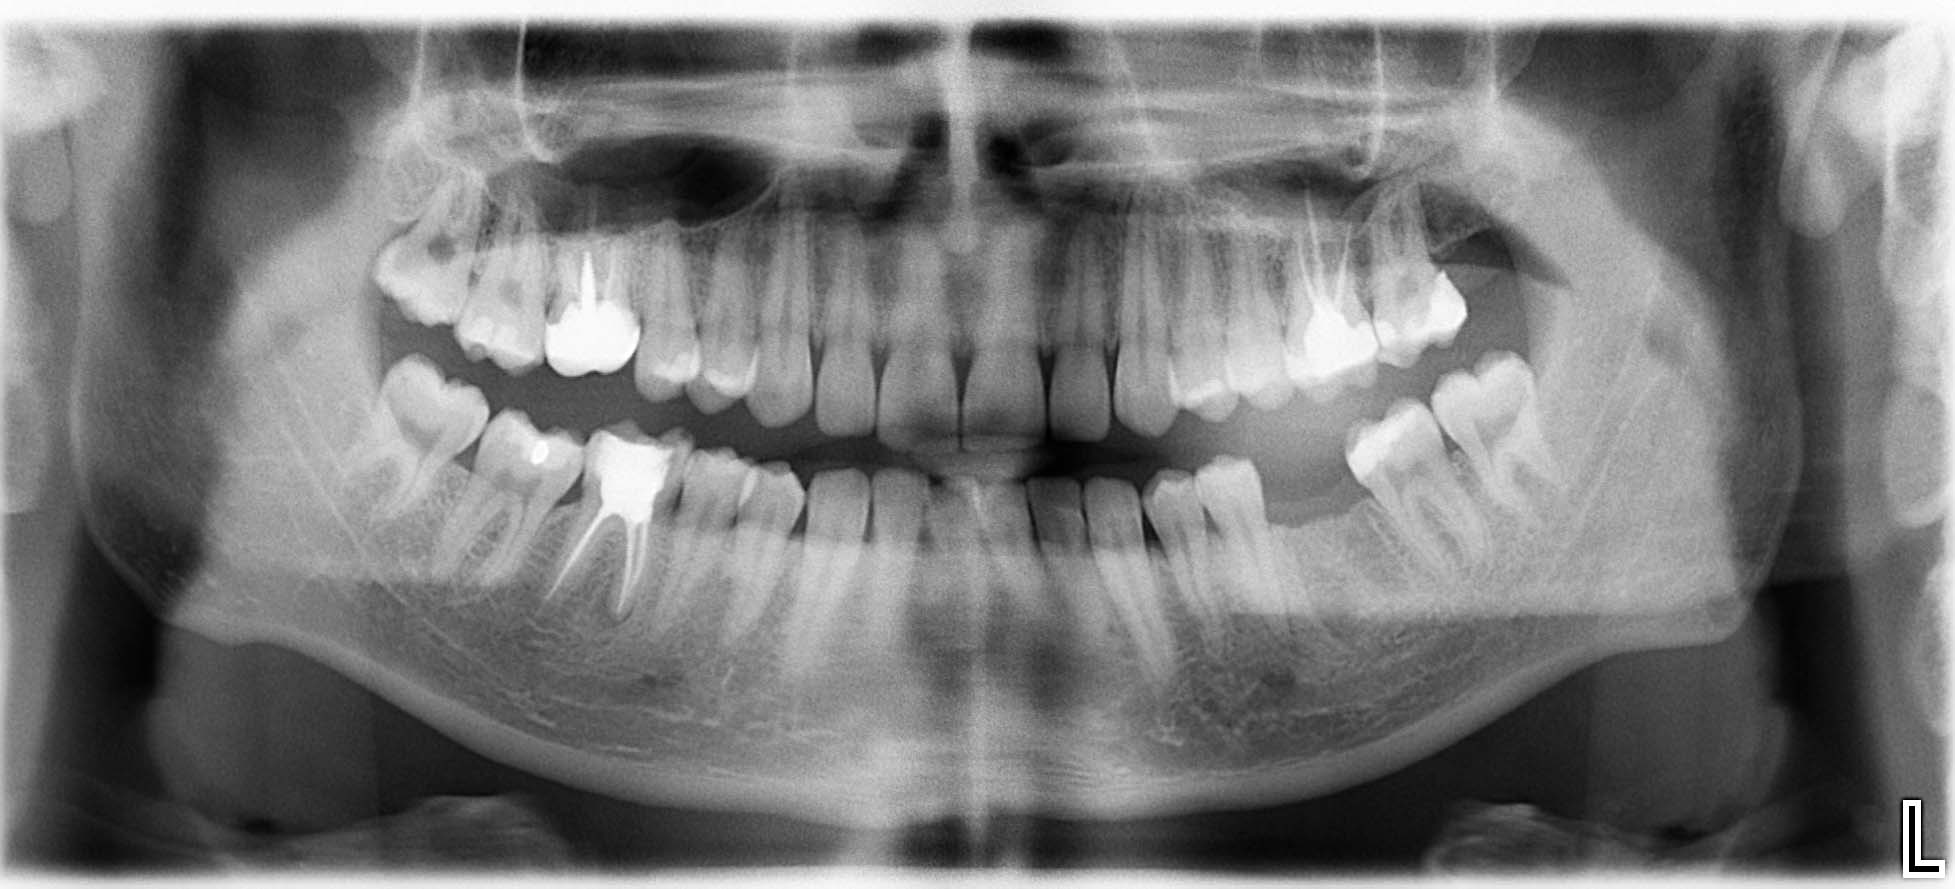

Erfolgreich implantierte Patientenfälle (klinische Fotos)